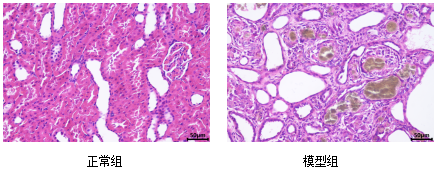

肾脏组织HE

Evaluation Criteria: Gross examination; Body weight and kidney index; Complete blood count; Renal tissue HE staining; Serum renal function markers